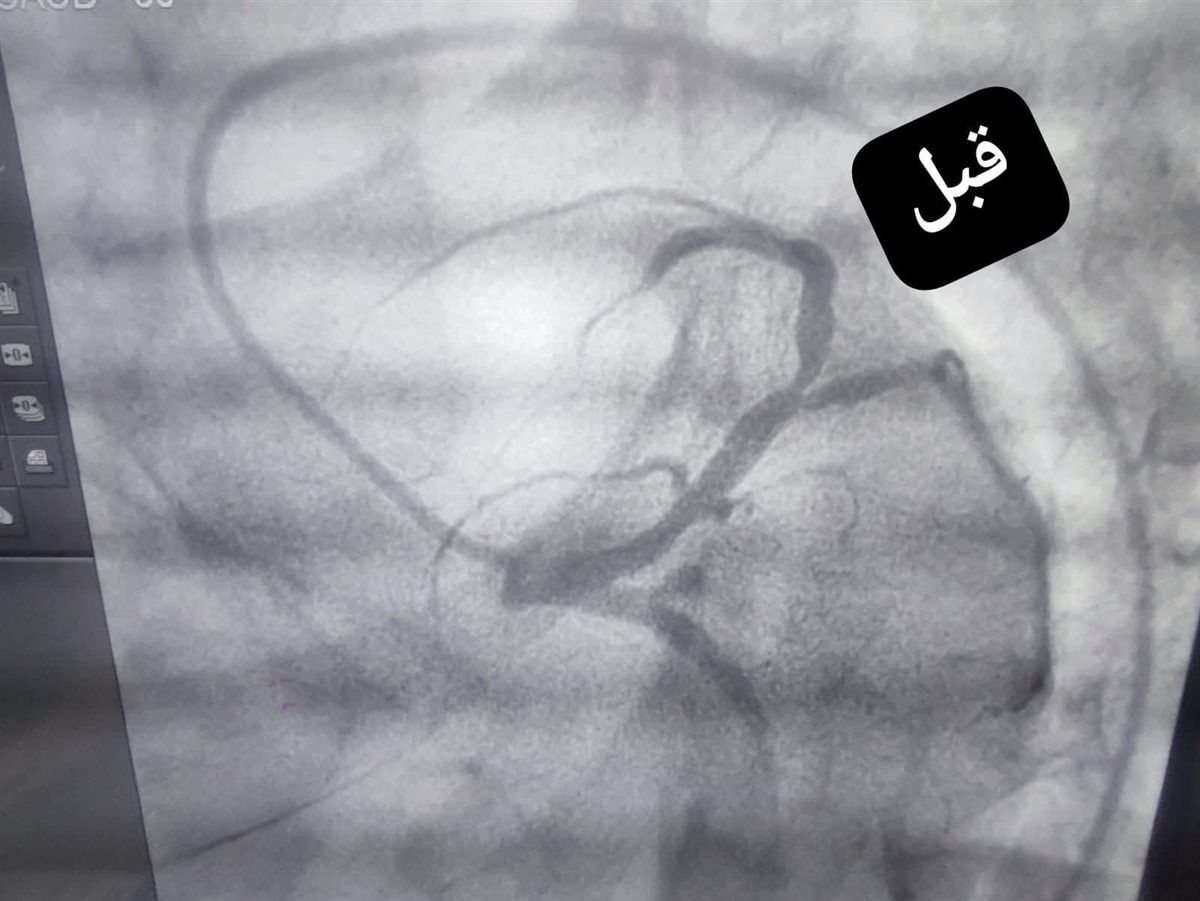

نجح الفريق الطبي بوحدة القسطرة القلبية بمستشفى قنا العام، فحالةى التعامل مع حالة حرجة لفتاة في مقتبل العمر، حيث أظهرت الفحوصات ورسم القلب إصابتها بجلطة حادة مع انسداد كامل في الشريان التاجي الأمامي الرئيسي، وهو ما استدعى التدخل الفوري لإنقاذ حياتها.

وعلى الفور، باشر فريق الإنعاش التعامل مع الحالة، وتمكن من إعادة النبض بنجاح، لتُجرى بعدها قسطرة قلبية علاجية عاجلة، أسفرت عن فتح الانسداد في الشريان التاجي الأمامي الرئيسي بنجاح تام.

وأسفر التدخل السريع عن تحسن ملحوظ في وظائف القلب، واستقرار الحالة الصحية للمريضة، التي غادرت المستشفى بعد أيام قليلة في حالة جيدة.